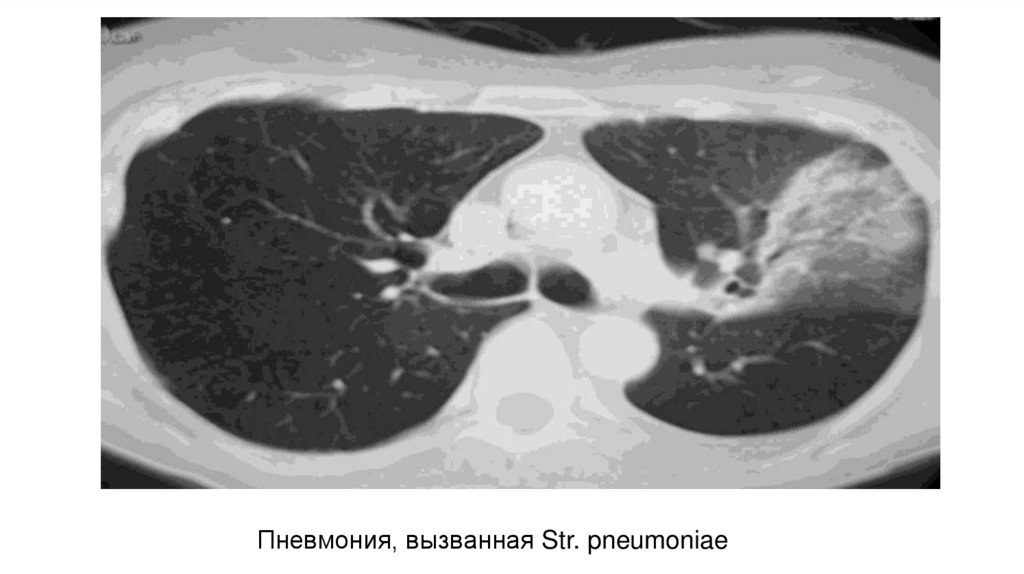

Пневмония, вызванная Str. pneumoniae